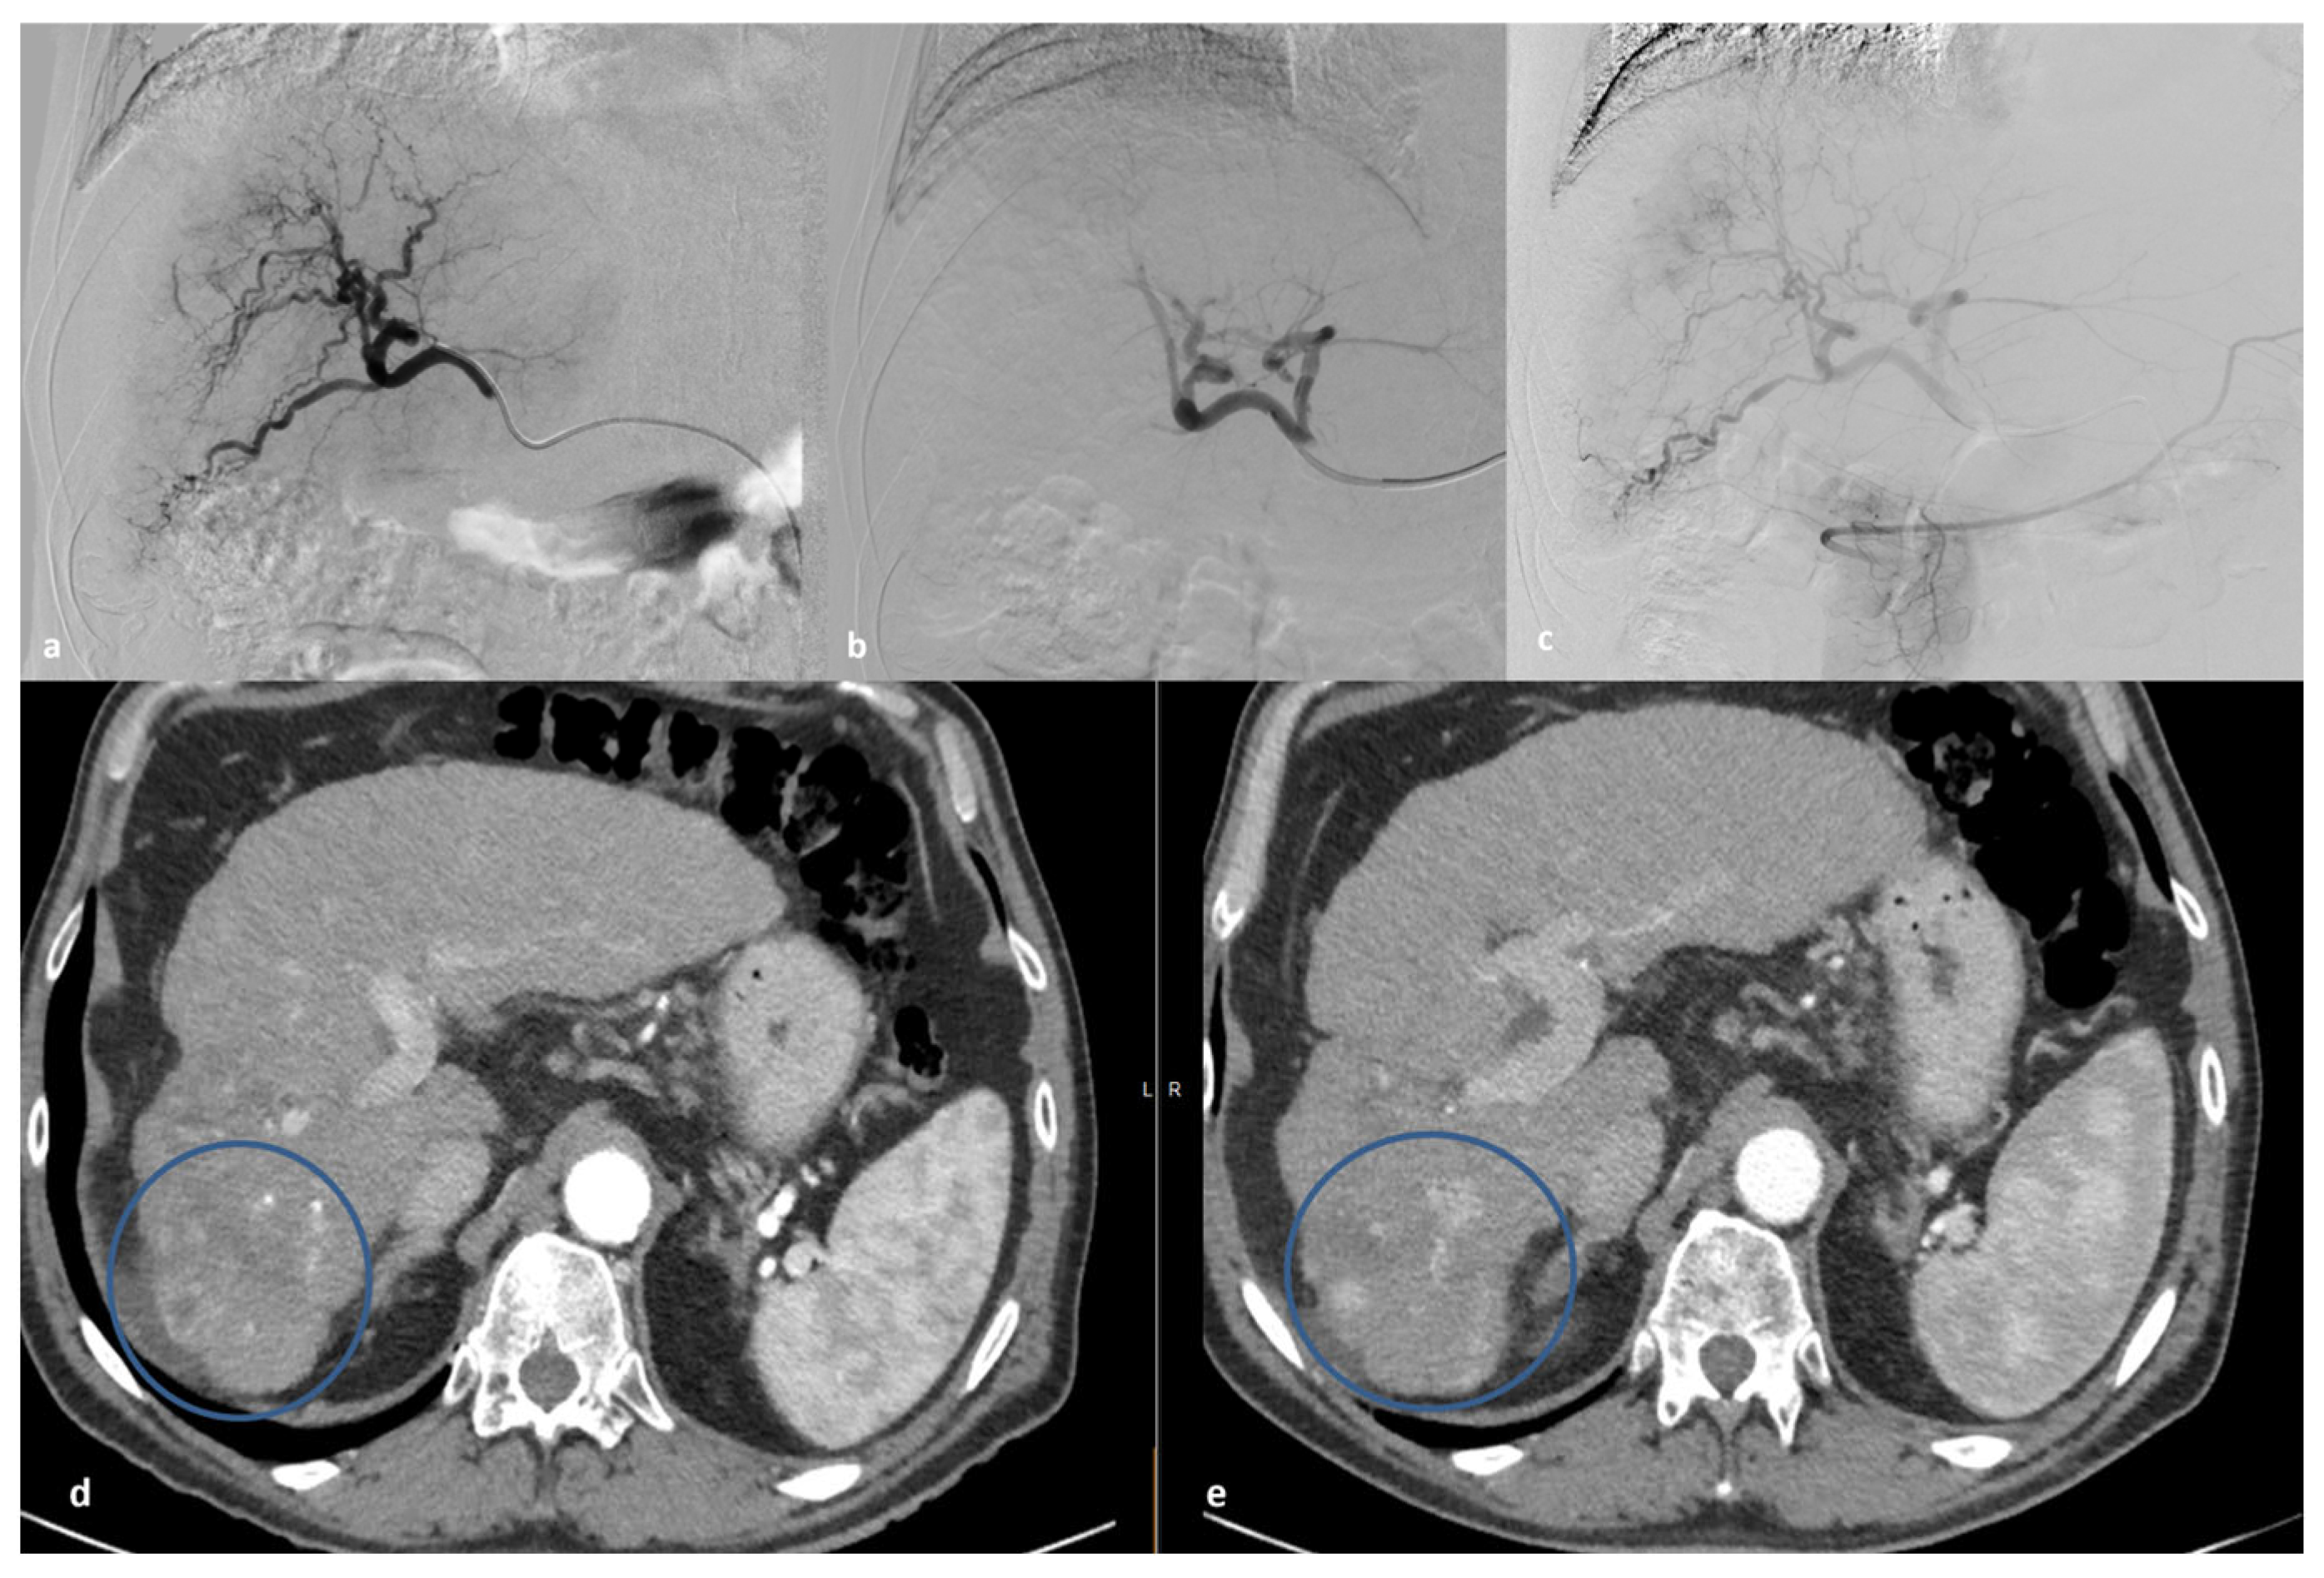

4. DMS-TACE Procedure

- Lucatelli, P.; De Rubeis, G.; Basilico, F.; Ginanni Corradini, L.; Corona, M.; Bezzi, M.; Catalano, C. Sequential dual-phase cone-beam CT is able to intra-procedurally predict the one-month treatment outcome of multi-focal HCC, in course of degradable starch microsphere TACE. Radiol. Med. 2019, 124, 1212–1219. [Google Scholar] [CrossRef] [PubMed]